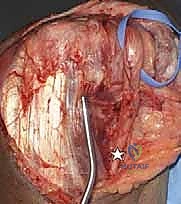

4. تركيب المفصل الصناعي التجريبي

قبل وضع المفصل النهائي، يتم وضع مفصل "تجريبي" لاختبار نطاق الحركة، واستقرار المفصل، وشد الأربطة. هذه الخطوة تضمن عدم وجود أي إعاقة للحركة بعد العملية.

5. تثبيت المفصل النهائي (الإسمنت العظمي)

يتم استخدام المفصل الصناعي النهائي، والذي يتكون غالباً من سبيكة معدنية عالية الجودة (مثل الكوبالت والكروم أو التيتانيوم) مع بطانة من البولي إيثيلين لضمان حركة سلسة. يتم تثبيت جذوع المفصل داخل العظام باستخدام "الإسمنت العظمي الطبي" (Bone Cement) الذي يضمن ثباتاً فورياً وقوياً، وهو أمر حاسم لمرضى هشاشة العظام.

6. ربط المفصل وإغلاق الجرح

بعد جفاف الإسمنت، يتم ربط جزئي المفصل (العضد والزند) معاً بمحور معدني (Linked Prosthesis)، مما يمنع خلع المفصل مستقبلاً. يعيد الدكتور هطيف بناء الأوتار (خاصة وتر العضلة الثلاثية) بدقة متناهية، ثم يتم إغلاق الجرح تجميلياً.